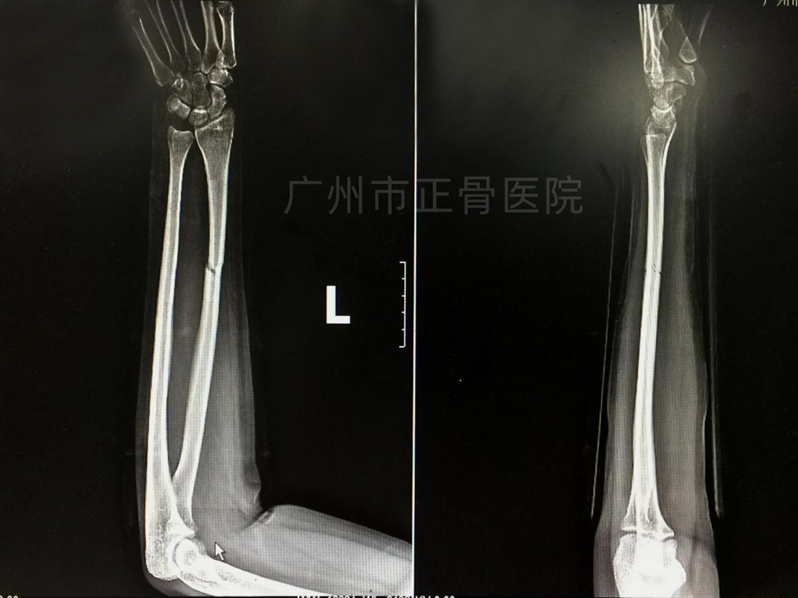

X线片检查结果:左桡骨中下段骨折,骨折远端向尺侧、掌侧成角移位,断端明显重叠短缩,周围软组织肿胀。

▲复位前,骨折端成角移位